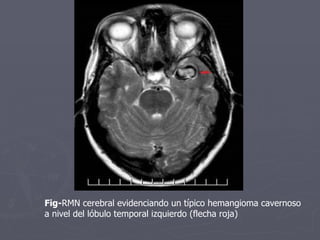

Fig- RMN cerebral evidenciando un típico hemangioma cavernoso  a nivel del lóbulo temporal izquierdo (flecha roja)

RM: Lesión con aspecto tipo nodular Hipointenso en T1, Rodeado de un Halo de Hemosiderina.

Fig- RMN cerebralevidenciando un típico hemangioma cavernoso a nivel del lóbulo temporal izquierdo (flecha roja)

RM: Lesión conaspecto tipo nodular Hipointenso en T1, Rodeado de un Halo de Hemosiderina.